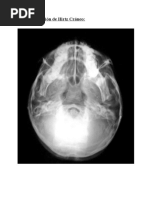

OJO CRISTALINO

La catarata u opacificación del cristalino

es una de las principales causas de

impedimento visual y ceguera. Puede ser

clasificada de tres formas: nuclear,

cortical y subescapular posterior (SCP) de

acuerdo con su localización anatómica.

La SCP esta asociada a exposición a

radiación ionizante.

La catarata u o pacificación del cristalino es una de las principales causas de

impedimento visual y ceguera y puede ser clasificadas en tres formas :

1.NUCLEAR 2.CORTICAL 3.SUBESCAPULAR POSTERIOR (SCP).

de acuerdo a su localización anatómica , la SCP es la menos común y esta asociada

a exposición a radiación ionizante. los cambios en el cristalino generalmente

aparecen en la zona (SCP), y consisten en pequeños puntos y vacuolas, que con e

tiempo se agregan para formar opacidades más grandes tanto la gravedad de la

catarata como su latencia están relacionados con la dosis recibida.